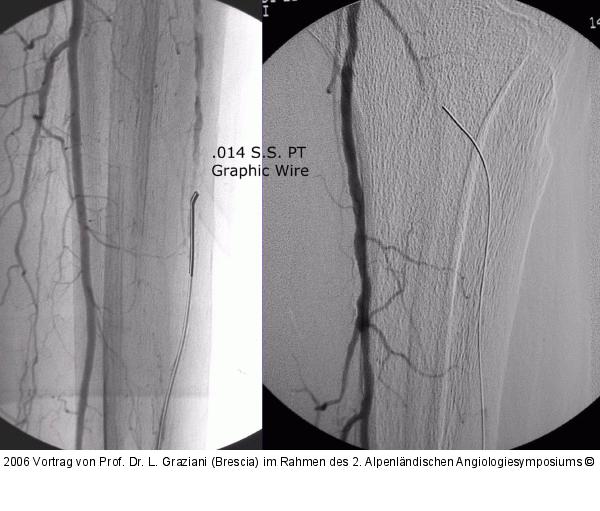

Vortrag von Prof. Dr. L. Graziani (Brescia) im Rahmen des 2. Alpenländischen Angiologiesymposiums

PTA of the foot arteries in diabetics: Extremities Extreme Angioplasty

Abbildung 71: Arteria dorsalis pedis - Katheterisation